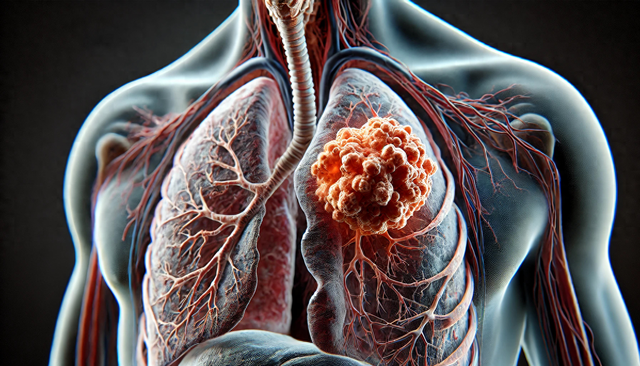

经过检查,李大爷被诊断出患有肺结节。医生告诉他,尽管肺结节本身并非一定是癌症,但它却是一个重要的警示信号,可能预示着肺部出现了某些问题。幸运的是,李大爷的肺结节处于早期,并且通过合理的治疗和生活方式调整,避免了病情进一步恶化。

肺结节的发生往往没有明显的症状,但身体却会给出一些微妙的信号。今天,我们就来了解一下,肺结节可能带来的4个“预警”,及时识别这些信号,能够帮助我们及早进行检查和治疗,防止病情加重。

呼吸急促或气短是肺结节常见的初期症状。李大爷起初并没有把这种现象当回事,认为只是年纪大了体力不支。然而,如果您在平时活动中经常感到气短,特别是在轻微运动后出现呼吸急促,那么很有可能是肺部出现了问题。肺结节可能压迫肺部气道,导致氧气交换困难,表现为呼吸困难。若出现这种症状,应尽早去医院检查,排查肺结节等肺部疾病。

肺结节患者有时会出现持续的干咳症状,尤其是在没有明显感冒或上呼吸道感染的情况下。这种干咳往往是没有痰的,且难以缓解。干咳可能是由于肺部受到刺激或炎症引起的,如果持续时间较长,特别是伴随体重下降或夜间症状加重时,应该警惕肺结节或其他肺部疾病的可能。

胸痛也是肺结节的一种常见症状。尽管大多数肺结节患者并不会感到明显的胸痛,但如果结节靠近肺部的胸膜,可能会引起局部的疼痛或压迫感。李大爷在散步时曾经感到胸部偶尔有些不适,这可能与肺结节有关。如果胸部疼痛持续存在,且无法通过休息缓解,或者伴随呼吸困难、咳嗽等症状,务必尽早就医。

肺结节虽然在初期可能没有明显的症状,但随着病情的进展,患者可能会出现不明原因的体重下降。体重骤降可能是由于肺结节导致的代谢异常,或是肺部功能受损所致。如果您没有进行过节食或剧烈运动,而体重却在短期内明显下降,这可能是肺结节的一个信号。